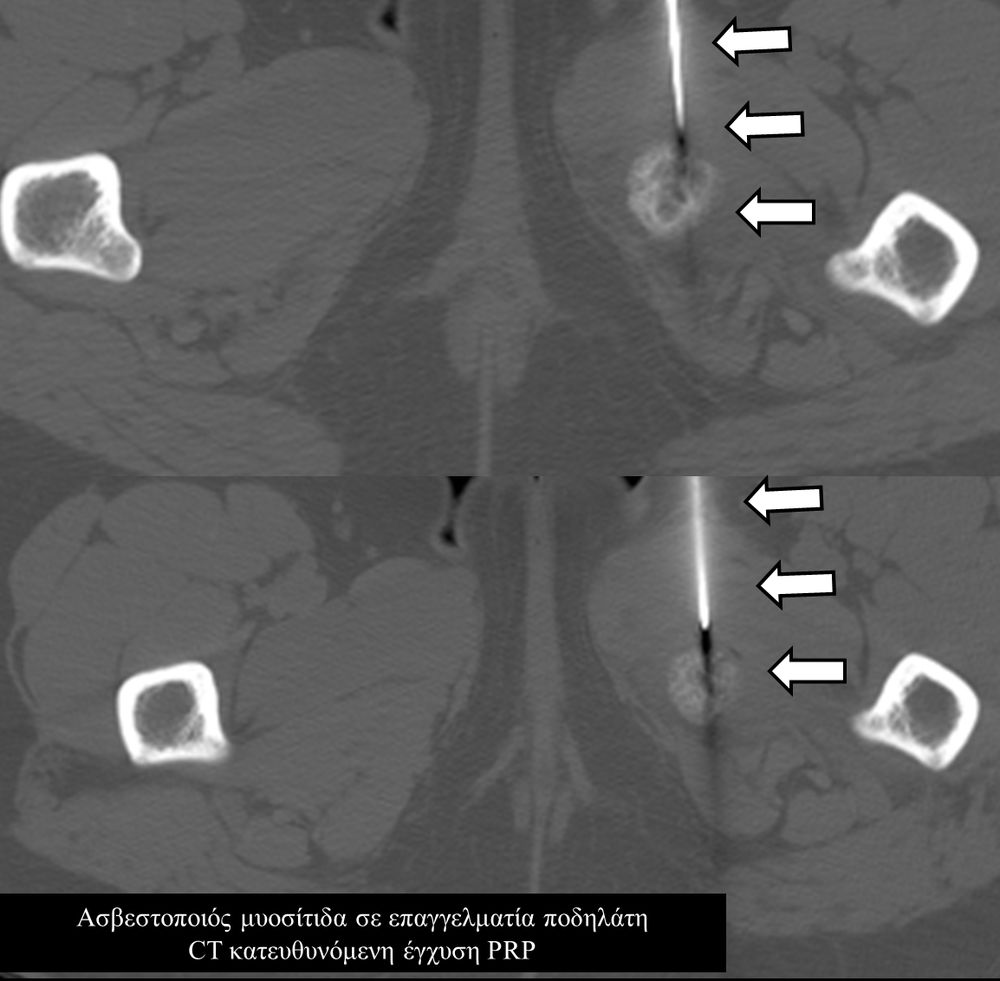

Οι κατευθυνόμενες εγχύσεις σε αθλητικές κακώσειςαποσκοπούν στη μείωση του πόνου, την ενίσχυση της αποτελεσματικότητας της φυσικοθεραπείας και την επιτάχυνση της διαδικασίας επούλωσης για την πιο γρήγορη επάνοδο του αθλητή στις αθλητικές του δραστηριότητες. Η πιο διαδεδομένη έγχυση αποτελεί η έγχυση PRP.Ανήκει σε μια σύγχρονη θεραπευτική μέθοδο γνωστή ως Ορθοβιολογική θεραπεία και βασίζεται την ικανότητα του οργανισμού να θεραπεύεται με τα δικά του αποκλειστικά θεραπευτικά μέσα χωρίς να υπάρξει χρήση φαρμάκων.Το PRP (Platelet Rich Plasma)-πλάσμα πλούσιο σε αιμοπετάλια- σήμερα αποτελεί μια θεραπευτική μέθοδο πρώτης γραμμής με σχετικά μεγάλη επιτυχία για την επούλωση τραυματισμένων τενόντων, μυών και εκφυλιστικών παθησεων όπως οστεοαρθρίτιδα.Η εφαρμογή του περιλαμβάνει μία ευρεία ποικιλία από παθήσεις όπως:

- Μυικές θλάσεις (οξείες και χρόνιες)